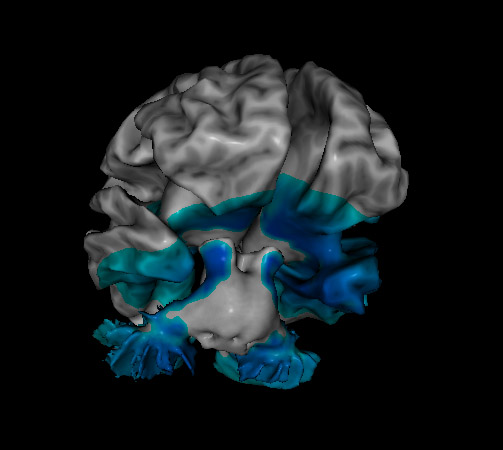

blue areas of brain represent depression from QEEG EEG scan showing signs of depression loreta neurofeedback showing the brain with depression what having depression looks like in your brain with loreta neurofeedback